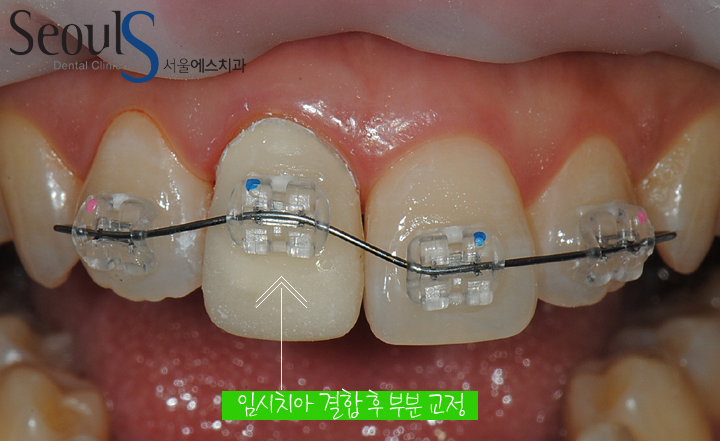

임시크라운을 씌우고 교정장치를 부착해

임시크라운을 씌우고 교정장치를 부착해

바람직한 위치로 치아를 이동시키고 있습니다

부분교정이 거의 마무리 된 모습으로

부분교정이 거의 마무리 된 모습으로

치아는 바람직한 방향으로 이동되었습니다